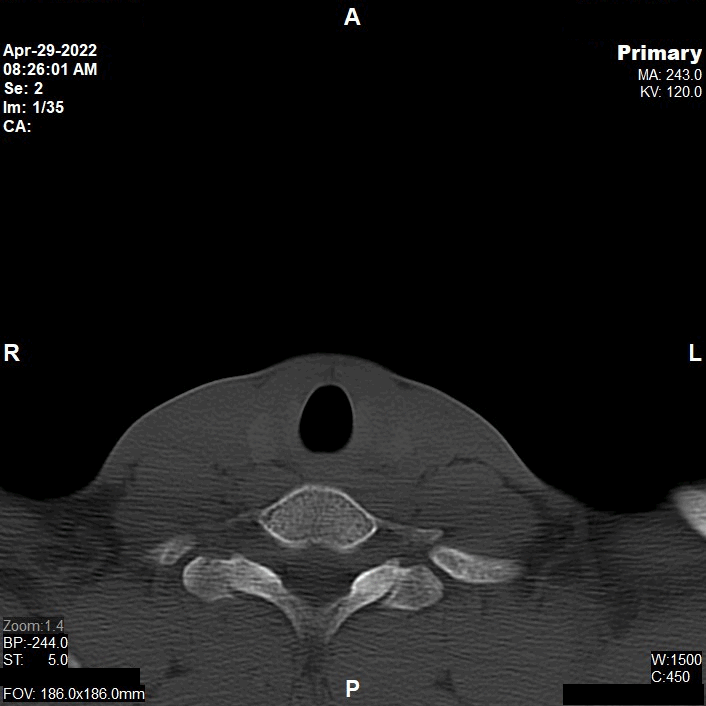

Appearance of Facial Bone in Axial CT Image

CT of Facial Bone

Reconstruction of Non Contrast

Reconstruction of Post Contrast

Multiplanar Reconstruction (MPR)

Series of Images Send to PACS

1. Topogram 0.6 T20f

2. Facial Bone NC 5.0 H60s

3. Facial Bone NC 5.0 H30s

4. Facial Bone NC 1.0 H60s

5. Facial IV 5.0 H30s

6. Facial IV 1.0 H30s